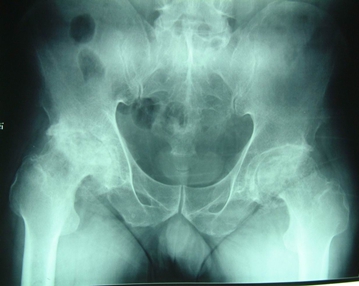

图1.双侧股骨头缺血性坏死